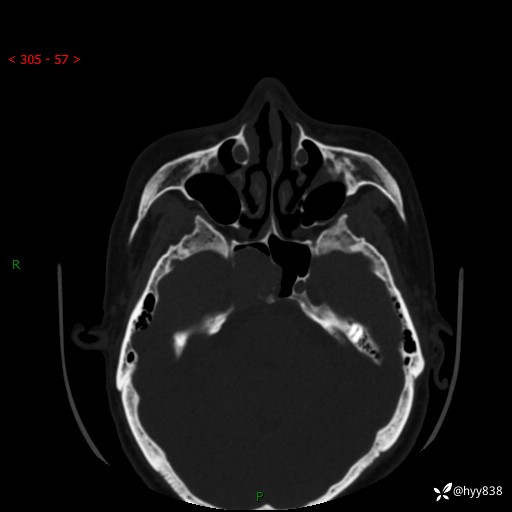

蝶鞍CT平扫